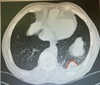

3

4